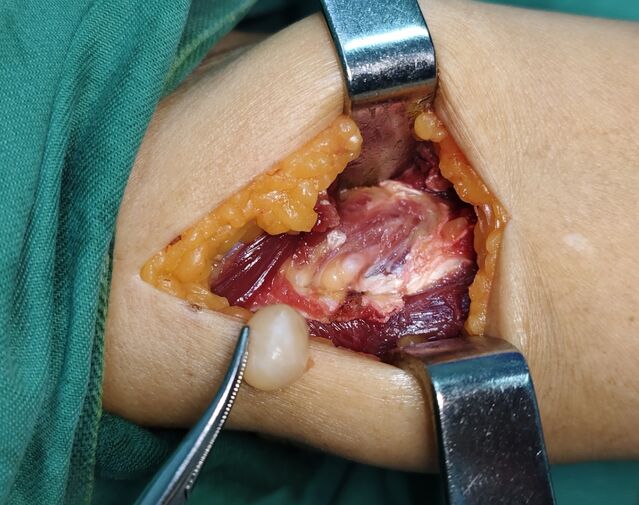

前臂近端背侧肿瘤,位于旋后肌内,紧贴桡骨颈部位

复习层次解剖: